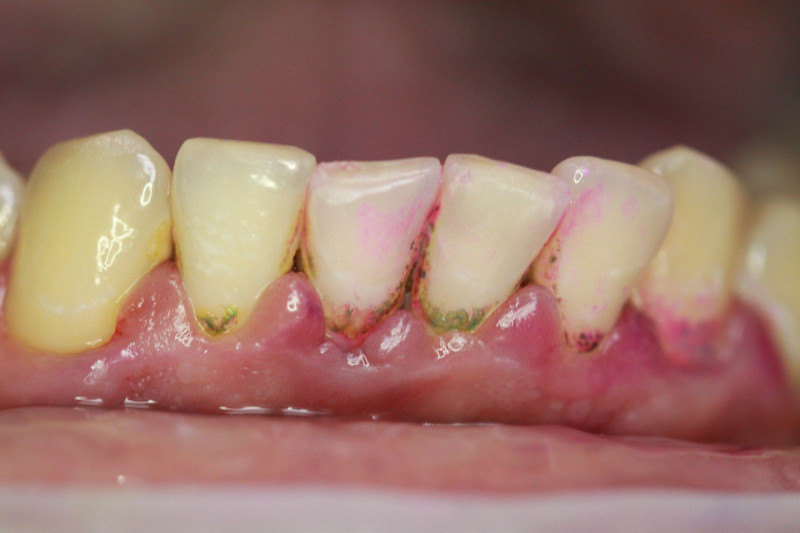

Index Dual работает по принципу селективного окрашивания: свежий налёт (до 24 часов) становится розовым, а зрелый кариесогенный налёт (более 24 часов) — синим.

Высокая контрастность Хорошо видно даже в пришейной зоне

Index Dual — это диагностический маркер, предназначенный для идентификации зрелости зубных отложений. В современной стоматологии это «детектор лжи» для пациента и навигационная карта для врача. Без использования подобных средств эффективность профессиональной чистки снижается, поскольку до 30% налёта остаётся незамеченным в межзубных промежутках и поддесневой зоне.

• Терапия: Используйте Index Dual перед реставрацией. Если после очищения на эмали остаётся синий пигмент — адгезия будет нарушена. Это ваш маркер качества подготовки полости.